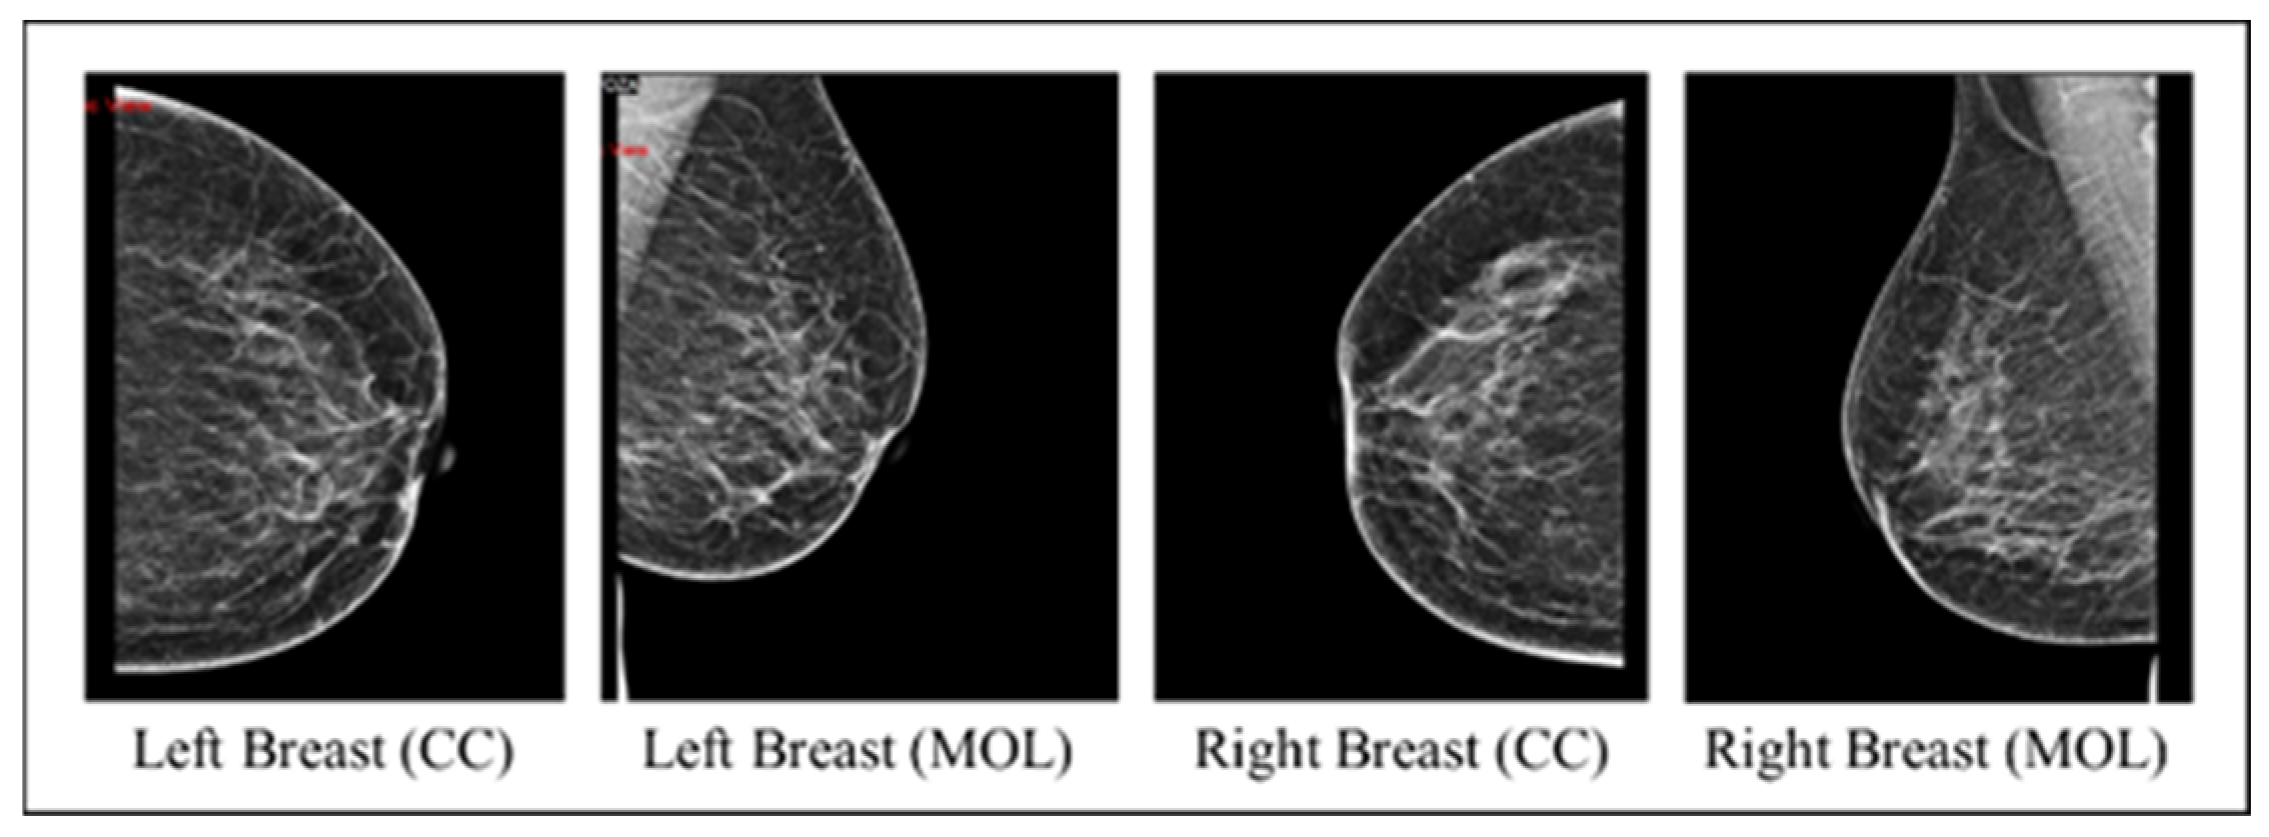

The collected images dataset includes four mammography views for each record, with CC and MLO views for both breasts (an instance on Figure 2). The images dataset went through many preprocessing steps as follows:

Figure 2.

An instance of the four mammography views for a record.